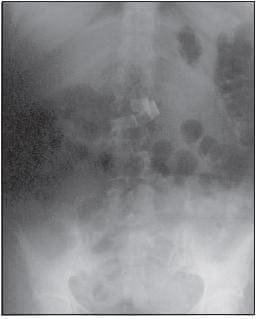

Caso 6: se trata de una paciente de sexo femeninode 50 años de edad, que presentaba dolor abdominalconstante, de 20 días de evolución asociado a episodios eméticos (de contenido alimentario), melenas, palidez mucocutánea, sensación de llenura y fiebre (40ºC). Tenía como antecedente una colecistectomía realizada por laparotomía supraumbilical 8 meses antes. Además de los exámenes paraclínicos, se le practicaron, en su orden: tomografía y ecografía abdominales, endoscopia digestiva alta y, finalmente, (por interés académico) un estudio radiológico simple de abdomen. En la ecografía hepato-biliar se encontraron cambios posoperatorios de colecistectomía. La tomografía axial computadorizada con contraste fue reportada como normal, con “vesícula y vías biliares sin alteraciones” (contrario al antecedente de colecistectomía) (figura 1).

FIGURA 1 A, B, C Y D. Tomografía de abdomen con contraste, con evidencia de “masa” a nivel del hígado con pared bien definida, contornos nítidos, niveles hidroaéreos, espongiforme y signos de inflamación periférica. En la figura 1d se observa una imagen aumentada de intensidad que corresponde a material radiopaco.